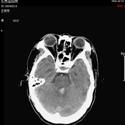

1).硬膜外血肿 术前 术后

2).颅后窝血肿术前 术后